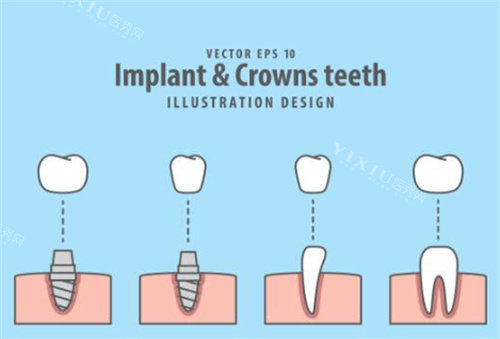

all - on - 4 半口种植牙技术是通过在上下颌各植入 4 颗种植体(后牙区两颗倾斜),利用力学原理搭建拱形牙桥,实现半口牙齿的修复。这种技术无需植骨,特别适合牙槽骨萎缩的中老年人。在东莞博医美口腔,all - on - 4 半口种植牙费用为 4 万元起。相比传统种植方案,它大大节省了费用,约可节省 30% 以上。

该技术还能实现即刻负重,患者当天就能戴上临时牙冠,术后 3 个月更换长久牙冠,极大缩短了无牙期。费用构成方面,植体费用约占 40%,牙冠(建议选择全瓷冠)和手术费各占 30%。